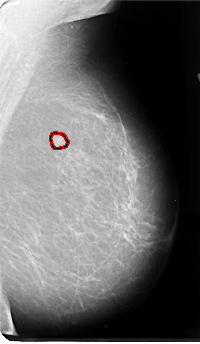

B_3071_1.LEFT_MLO

LEFT_CC LINES 4800 PIXELS_PER_LINE 2816 BITS_PER_PIXEL 12 RESOLUTION 50 OVERLAY

LEFT_MLO LINES 4808 PIXELS_PER_LINE 2800 BITS_PER_PIXEL 12 RESOLUTION 50 OVERLAY

FILE: B_3071_1.LEFT_MLO.OVERLAY

TOTAL_ABNORMALITIES 1

ABNORMALITY 1

LESION_TYPE MASS SHAPE IRREGULAR MARGINS SPICULATED

ASSESSMENT 4

SUBTLETY 4

PATHOLOGY MALIGNANT

TOTAL_OUTLINES 1

BOUNDARY

FILE: B_3071_1.LEFT_CC.OVERLAY